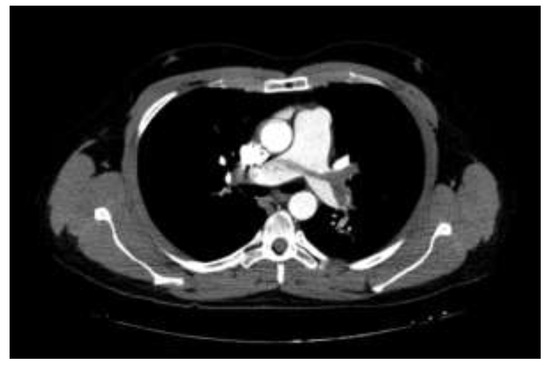

Pulmonary CT Angiography